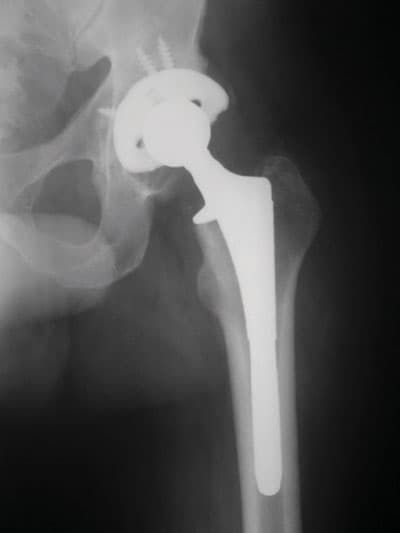

إن عمليات المفاصل من العمليات الشائعة في الغرب وأكثرها في مفصل الورك والركبة والكتف والكوع والفائدة الرئيسة للمفصل الصناعي هي تناقص الألم المستمر، ويشعر أن الطرف أصبح أقوى من قبل، وأن الحركة غير مؤلمة، كما يلاحظ كثير من المرضى تحسنا في حركة المفصل، ففي حالة مفصل الكتف الصناعي يلاحظ المريض أنه يستطيع بعد العمل الجراحي تسريح شعر رأسه والنظافة الشخصية وتغيير ملابسه دون مساعدة ويستطيع رفع الأشياء بشكل أفضل، أما في حالة مفصل الورك والركبة فإن المريض يستطيع المشي دون ألم لمسافات طويلة وحركة المفصل تصبح أفضل ودون ألم كذلك فإن شكل الساق يصبح أفضل، حيث يكون قبل العملية مقوسا ويصبح بعد العمل الجراحي مستقيما وذا منظر طبيعي.

لقد أثبتت المفاصل الصناعية نجاحها، فقد تطورت تطوراً سريعاً خلال السنوات العشر الماضية ولقد بدأ استخدامها منذ 30 عاماً، ونظراً لما يعترض مفصل الركبة من إصابات تؤدي إلى تلفه فقد حصلت تطورات كثيرة على المفصل الصناعي للركبة خلال السنوات الخمس الماضية، والمفصل الصناعي للركبة يلائم صغار السن وأكثر ثباتاً. وإن أكثر مضاعفات جراحة الركبة هي الالتهابات، حيث تبلغ نسبة هذه المضاعفات 1 في المائة فقط في المراكز الطبية المتميزة، وهي نسبة ضئيلة ولكنها إن حدثت فهي مشكلة كبيرة، عندها قد نضطر إلى نزع المفصل الصناعي ونضع مكانه مضاداً حيوياً على شكل طبقة طبية، وقد يخضع المريض لفترة من العلاج قبل وضع المفصل الصناعي من جديد، كما تشمل بعض المضاعفات الأخرى كجلطات الدم في القدم التي من الممكن السيطرة عليها بشكل فاعل بالتحرك المبكر وباستخدام الأسبرين ومسيلات الدم الأخرى، وجعل المريض يتحرك مبكراً لمنع حدوث الاحتقان في الرئتين.

ومفصل الركبة من المفاصل المهمة التي تقوم بدور عظيم في حياة الإنسان، فعليها يتم حمل الجسم "إضافة إلى المفاصل الأخرى في الأطراف السفلية"، وهو مفصل دقيق ومعقد، وما يميزه من الناحية التشريحية عدم وجود طبقة عضلية سميكة تغطيه، وهذا ما يجعل عملية إجراء المفاصل الصناعية من الناحية العملية أمراً ليس بالهين، ويحتاج إلى الكثير من الخبرة والدقة لإجرائه، فهناك الكثير من النقاط التي يجب مراعاتها أثناء العمل الجراحي إلا أن التطورات الأخيرة في مجال المفاصل الصناعية ووجود نخبة من الجراحين وازدياد الخبرات في ذلك جعل نتائج العمليات أفضل بكثير من ذي قبل، وأصبح بإمكان الكثير من المرضى ممارسة حياتهم بشكل قريب جداً إلى المستوى الطبيعي، وعلى المريض أن يستشير طبيبه كي يساعده على اتخاذ القرار واللجوء إلى الحل الجراحي.